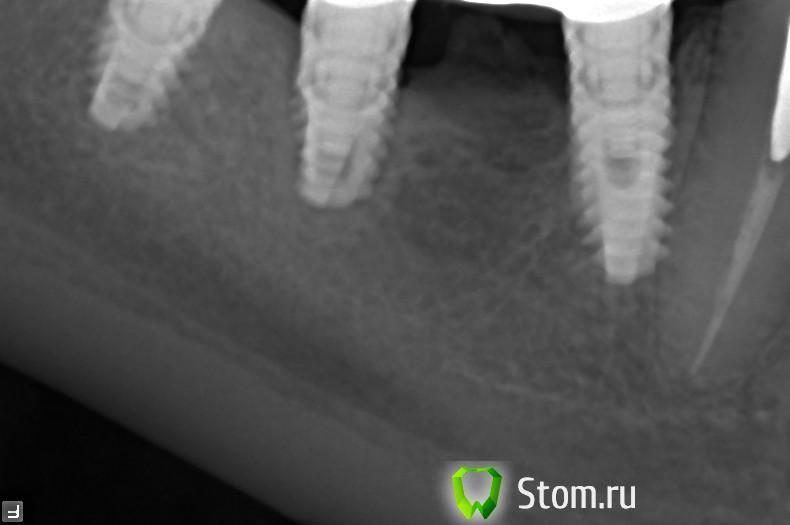

markol Опубликовано 4 апреля, 2012 Поделиться Опубликовано 4 апреля, 2012 Здравствуйте уважаемые специалисты столкнулся со странной проблемой! В 2008 г. успешно прошел имплантацию и протезирование. Всего 10 единиц. Новыми зубами был очень доволен. Месяц назад ел слишком твердую пищу (кусок вяленой рыбы) и при надкусывании вдруг снизу справа почувствовал неожиданно боль в том месте где стоит коронка на трех имплантах . Затем боль стала при каждом жевании пищи с этой стороны появлятся. После приема пищи все проходит. Воспаления десен и другого дискомфорта не испытываю . Сделал снимок и сходил в несколько клиник. В одной мне сказали что все нормально воспалительных явлений нет. В другой что средний имплант судя по снимку потерял связь с костной тканью и нужно его перекручивать. На снимке как бы в том месте где резьба нет связи с костью. Что делать не знаю! Прочитал что переимплантит сопровождается более явными воспалительными явлениями чего у меня не было. Ссылка на комментарий